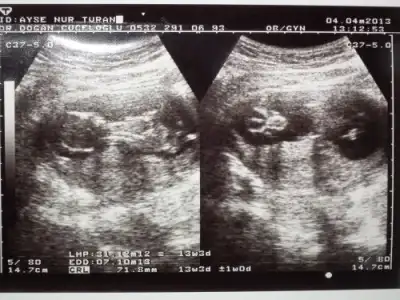

dr soylemeden siz gorun genital nub teorisi ( bebegin cinsiyeti)

13 hfta 3 gnlgz burda bi tahminin varmı canm önceki gönderdigme kız demiştin